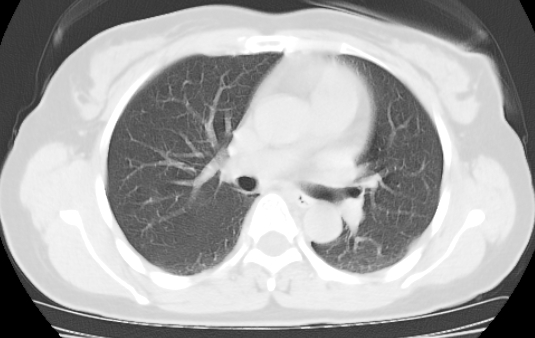

标题: CT25227:背部疼痛伴双侧胸壁痛2月,食欲差。 [打印本页]

标题: CT25227:背部疼痛伴双侧胸壁痛2月,食欲差。

肺结核并胸椎结核?请各位高手指教。

考虑胸椎结核并椎旁软组织肿胀。

椎旁软组织肿胀。

考虑胸椎结核并椎旁软组织肿胀。 支持